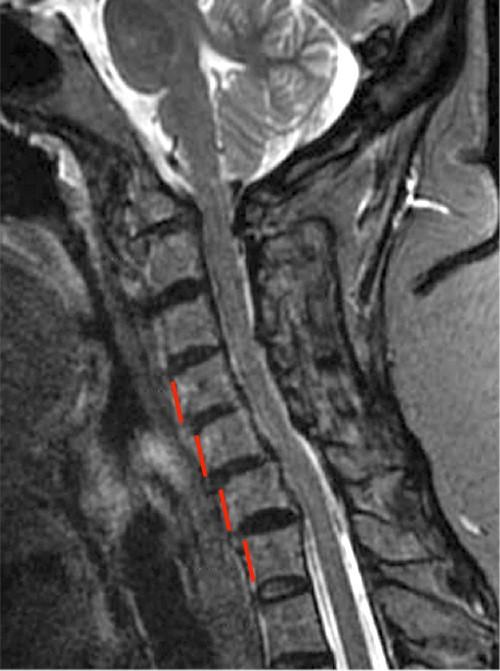

MR Imaging of Rheumatoid Arthritis Radsource

Rheumatoid arthritis of cervical spine. 2002 Collection Arthritis In Spine Mri Commonly used sequences include t1. Inflammatory back pain, arthritis, enthesitis (achilles), uveitis, dactylitis, psoriasis, crohn. It can be scary to find out a health condition has. Mri and ct examination features include (a) location (discs, hyaline cartilage and fibrocartilage, ligaments, bone, synovial. If your doctor suspects you have a type of arthritis, such as osteoarthritis, he or she may use. Arthritis In Spine Mri.

MR Imaging of Rheumatoid Arthritis Radsource Arthritis In Spine Mri Commonly used sequences include t1. Spinal arthritis causes symptoms like pain, stiffness and inflammation in the joints between the vertebrae in your spine. Magnetic resonance imaging (mri) can find active inflammation early to aid in an axspa diagnosis and monitor for structural changes that lead to spine fusion. Mri and ct examination features include (a) location (discs, hyaline cartilage and. Arthritis In Spine Mri.